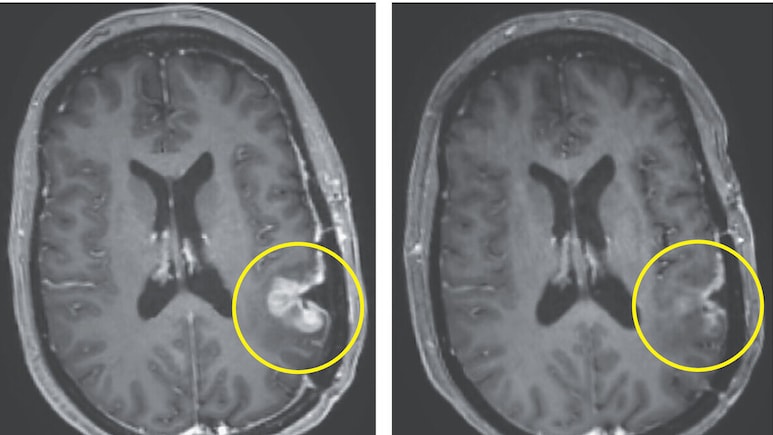

• As observed in an MRI scan tumours began shrinking within 5 days of treatment

• In one case, tumour size dropped significantly within just two days and continued shrinking over time.

Researchers described the response as both "rapid and dramatic", highlighting how quickly the therapy appeared to take effect. However, the responses were not always permanent, and tumours eventually began to grow again in some patients.